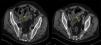

A 67-year-old man with a history of malignant pleural mesothelioma (T3N2M0) underwent radical pleuropulmonectomy with lymphadenectomy in July 2010. Adjuvant chemotherapy was administered and the patient was followed up by the Oncology department. He presented in the emergency room in August 2011 with a 4-h history of sudden onset abdominal pain, initially in the lower abdomen, but which then became diffuse. On examination, abdominal guarding with signs of peritoneal irritation were observed. Clinical laboratory test results were within normal limits. No significant findings were detected on abdominal X-ray. An abdominal computed tomography with intravenous contrast medium was performed, revealing air in the peritoneal cavity, circumferential wall thickening of a short segment of the hypogastric small intestine (jejunum) with marked inflammatory changes and small adjacent air bubbles (Fig. 1). In view of these findings, emergency laparoscopic intervention with supra and infra-umbilical access was performed, revealing acute purulent peritonitis in the inframesocolic space due to a single perforation of the jejunum at the site of an ischemic lesion. Intestinal resection with manual end-to-end anastomosis was performed and the post-operative period was incident-free. Pathology reported epithelioid malignant mesothelioma metastasis in the intestinal wall and 2 isolated lymph nodes. The patient was referred to the oncology department for treatment with chemotherapy.